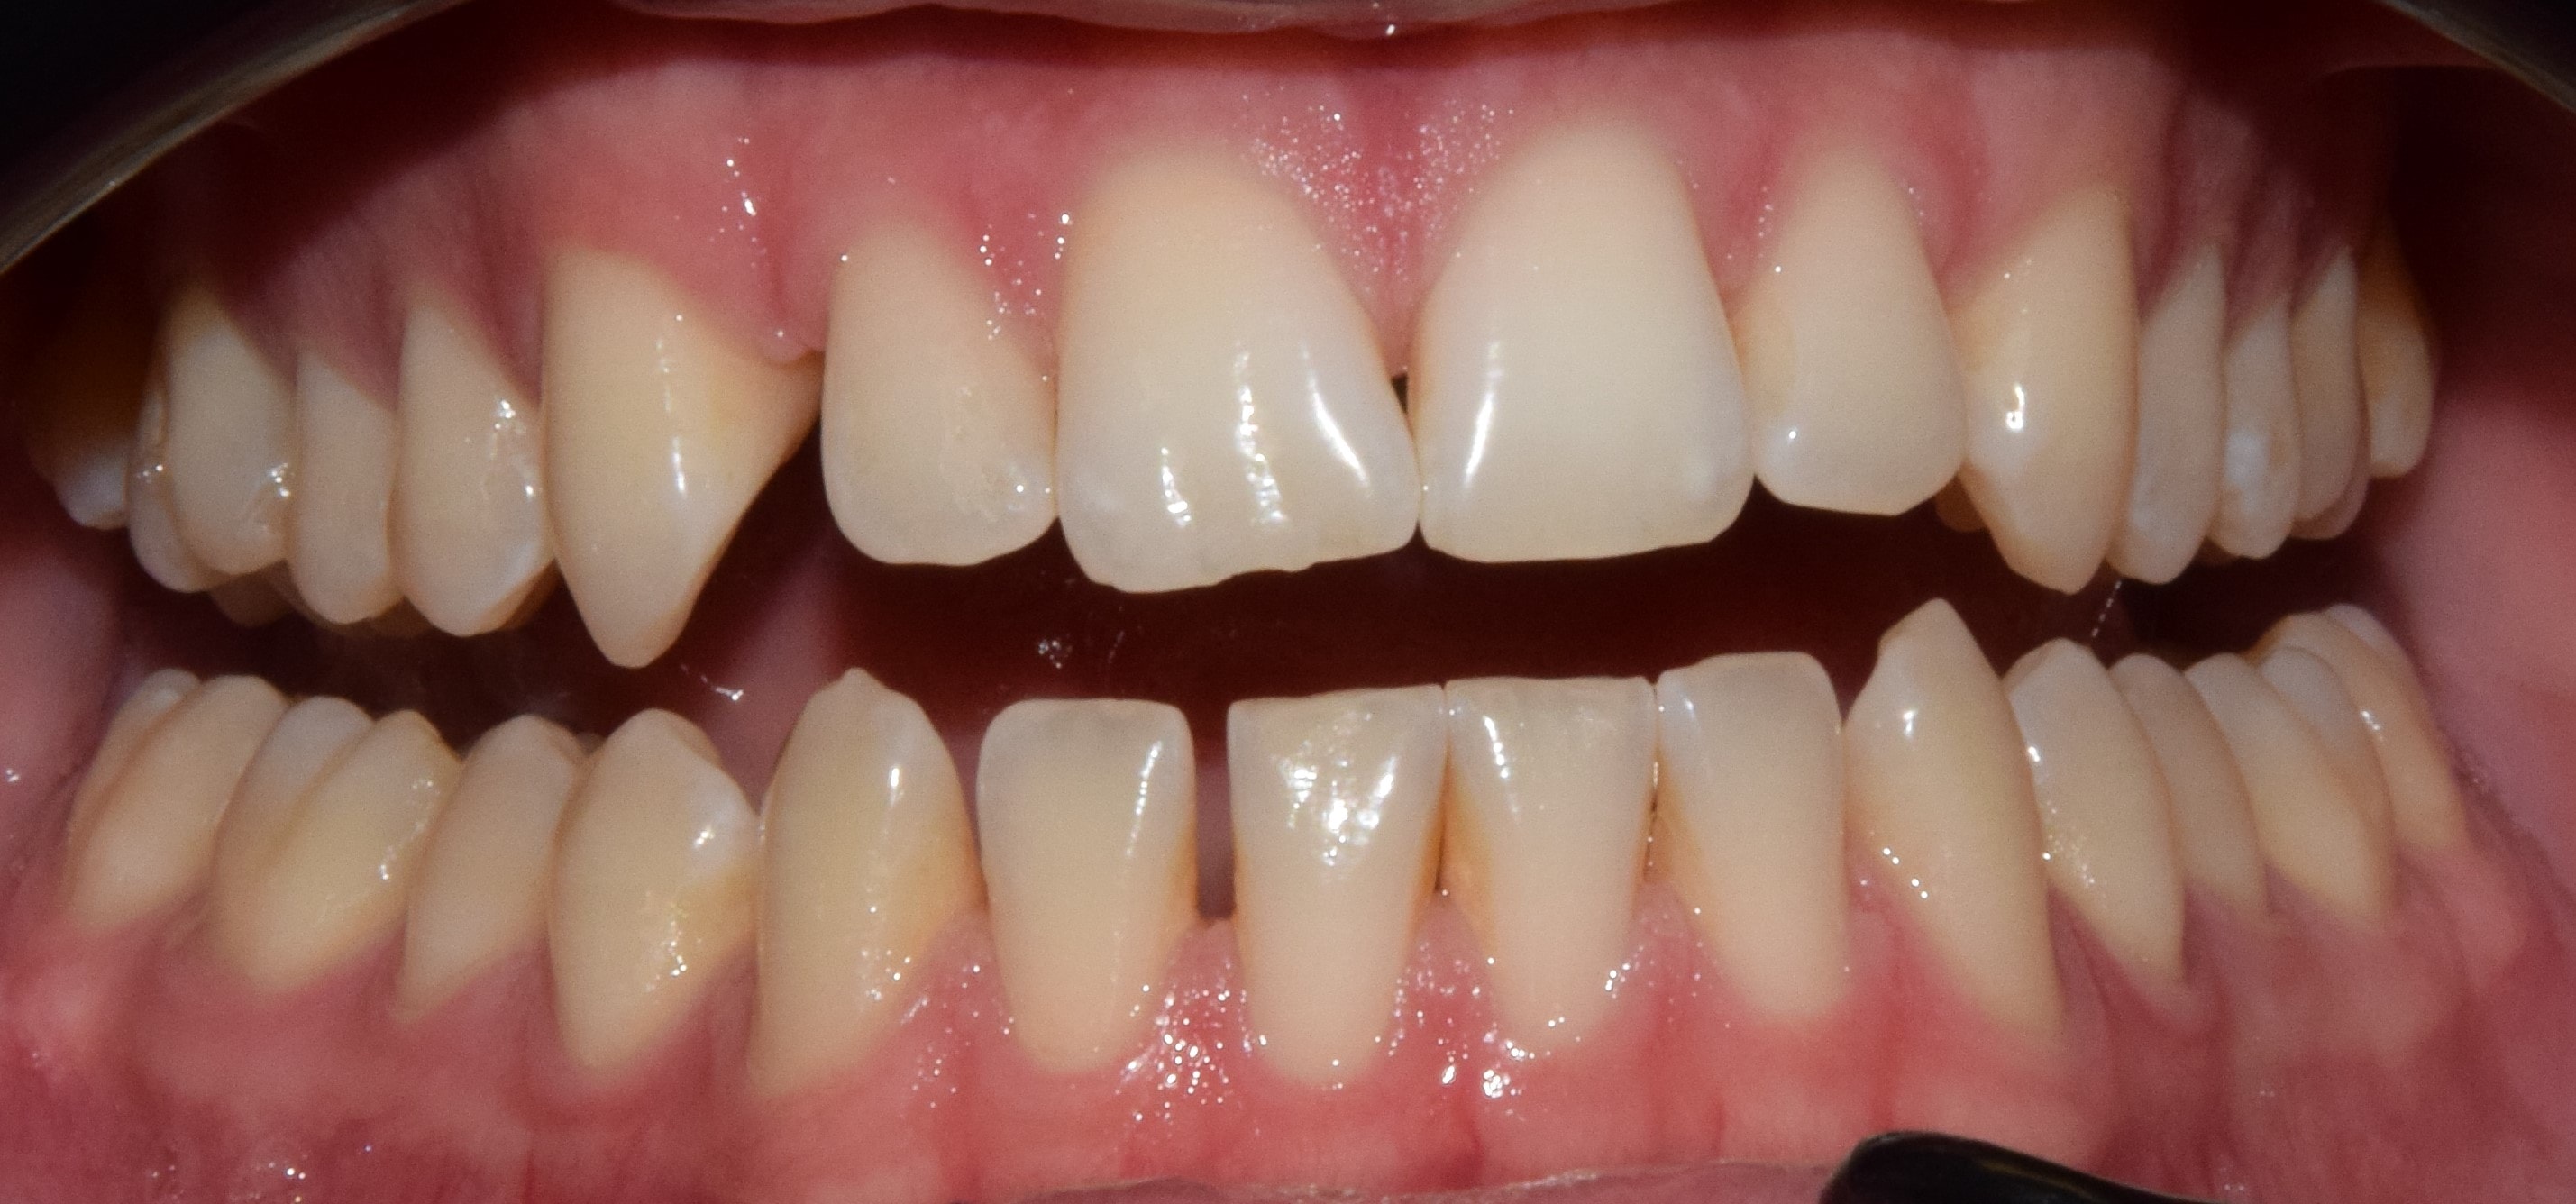

Nyitottharapás

Nyitottharapásnak nevezzük, amikor a felső és alsó fogak nem érintkeznek egymással. Ez lehet elülső nyitottharapás, mely tipikusan korábbi cumizás, vagy ujjszopás miatt alakul ki, valamint lehet oldalsó nyitottharapás, amit sokszor csírahiány okoz. Extrém esetben előfordulhat, hogy szinte teljes a nyitottharapás, csak a leghátsó (legtöbbször második őrlőfogak) érintkeznek egymással. Az overbite értéke negatív.